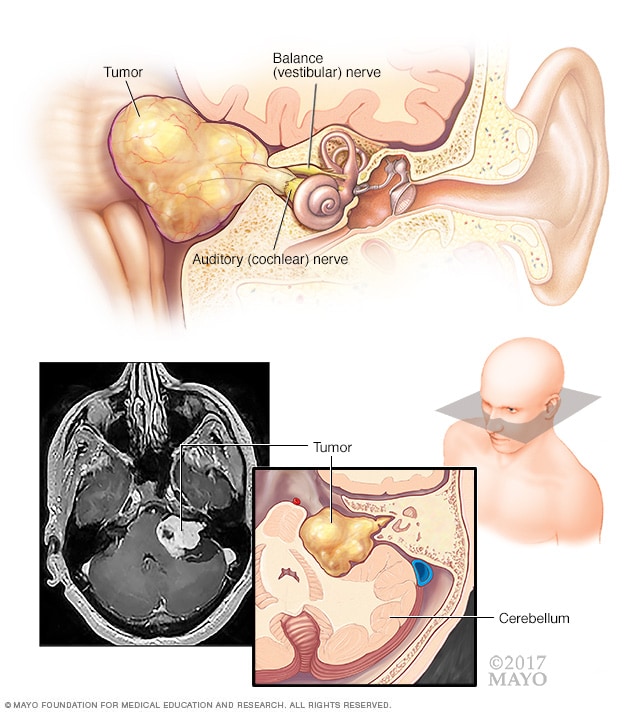

A brain tumor can form in the brain cells (as shown), or it can begin elsewhere and spread to the brain. As the tumor grows, it creates pressure on and changes the function of surrounding brain tissue, which causes signs and symptoms such as headaches, nausea and balance problems.

Acoustic neuroma (vestibular schwannoma)

An acoustic neuroma (vestibular schwannoma) is a benign tumor that develops on the balance and hearing nerves leading from the inner ear to the brain. These nerves are twined together to form the vestibulocochlear nerve (eighth cranial nerve). The pressure on the nerve from the tumor may cause hearing loss and imbalance.

- Nerve tumors. Nerve tumors are growths that happen in and around nerves. The most common type that happens in the head is acoustic neuroma , also called schwannoma. This benign tumor is located on the main nerve that connects the inner ear to the brain.